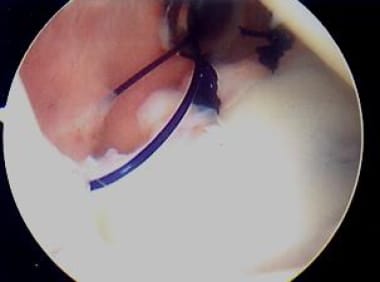

Next, with monofilament suture employed in an all-arthroscopic knot-tying technique (sliding knot first, backed up by an alternating post, alternating half-hitch technique), a knot is tied, plicating the capsular pinch to the labrum (see the image below).

Next, with monofilament suture and all-arthroscopic knot-tying technique, knot is tied, thus plicating capsular "pinch" to labrum. Photo courtesy of Daniel C Wnorowski, MD.

The process is repeated to place a second, slightly more superior suture and knot (see the images below). Capsular pinches or tucks may vary at the surgeon's discretion, and the number of sutures and the spacing between sutures also may vary (1-cm spacing is typical; see the images below). Caution is advised in passing sutures in the inferior regions anteriorly and posteriorly, given the proximity of the axillary nerve to the inferior capsule. It is best to avoid passing sutures altogether between the 5- and 6-o'clock positions.

Process in image above is repeated to place second, slightly more superior suture and knot. Photo courtesy of Daniel C Wnorowski, MD.